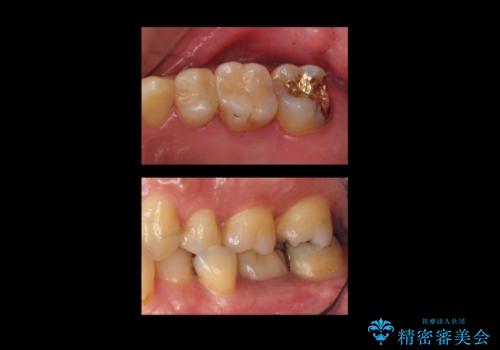

奥歯の詰め物のやりかえ セラミックインレー、ゴールドインレー

- 上の奥歯の詰め物が合っていないため、やりかえを行いました。

- 20万円 内訳 左上56:emaxインレー7万円x2 、左上7:PGAインレー6万円 (税別)費用は治療当時の料金となります

上の一番奥の歯は、一番目立たない場所なので(他人から見えない)、ゴールドインレーでも目立ちません。

セラミックインレーでは割れやすい大きさの虫歯または、歯が薄くなって被せなければいけないような場合でも、金属(ゴールド)は耐久性があり、クラウン(被せ物)にしなくて済みます。